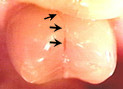

Cracked

tooth. When a tooth is cracked, a filling

will not seal the crack. A crown has to be placed over the tooth

to hold it and the crack together. If a crown is not placed on the

tooth, the tooth will become sensitive to chewing pressure, or will

eventually break. It is important to crown a cracked tooth before

it breaks, because in some cases a broken tooth cannot be crowned

and must be extracted. Cracked

This

patient chose not to have the cracked tooth above crowned, and it

later fractured. This tooth had to be extracted because it cracked

all the way to the root. This